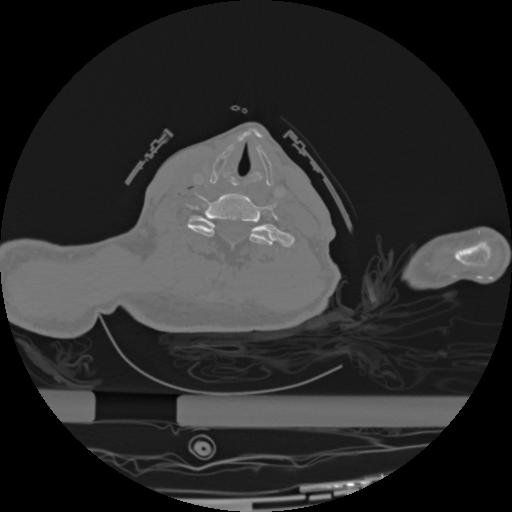

22 ANGIO,CE,Vol,0.5,ANGIO,,